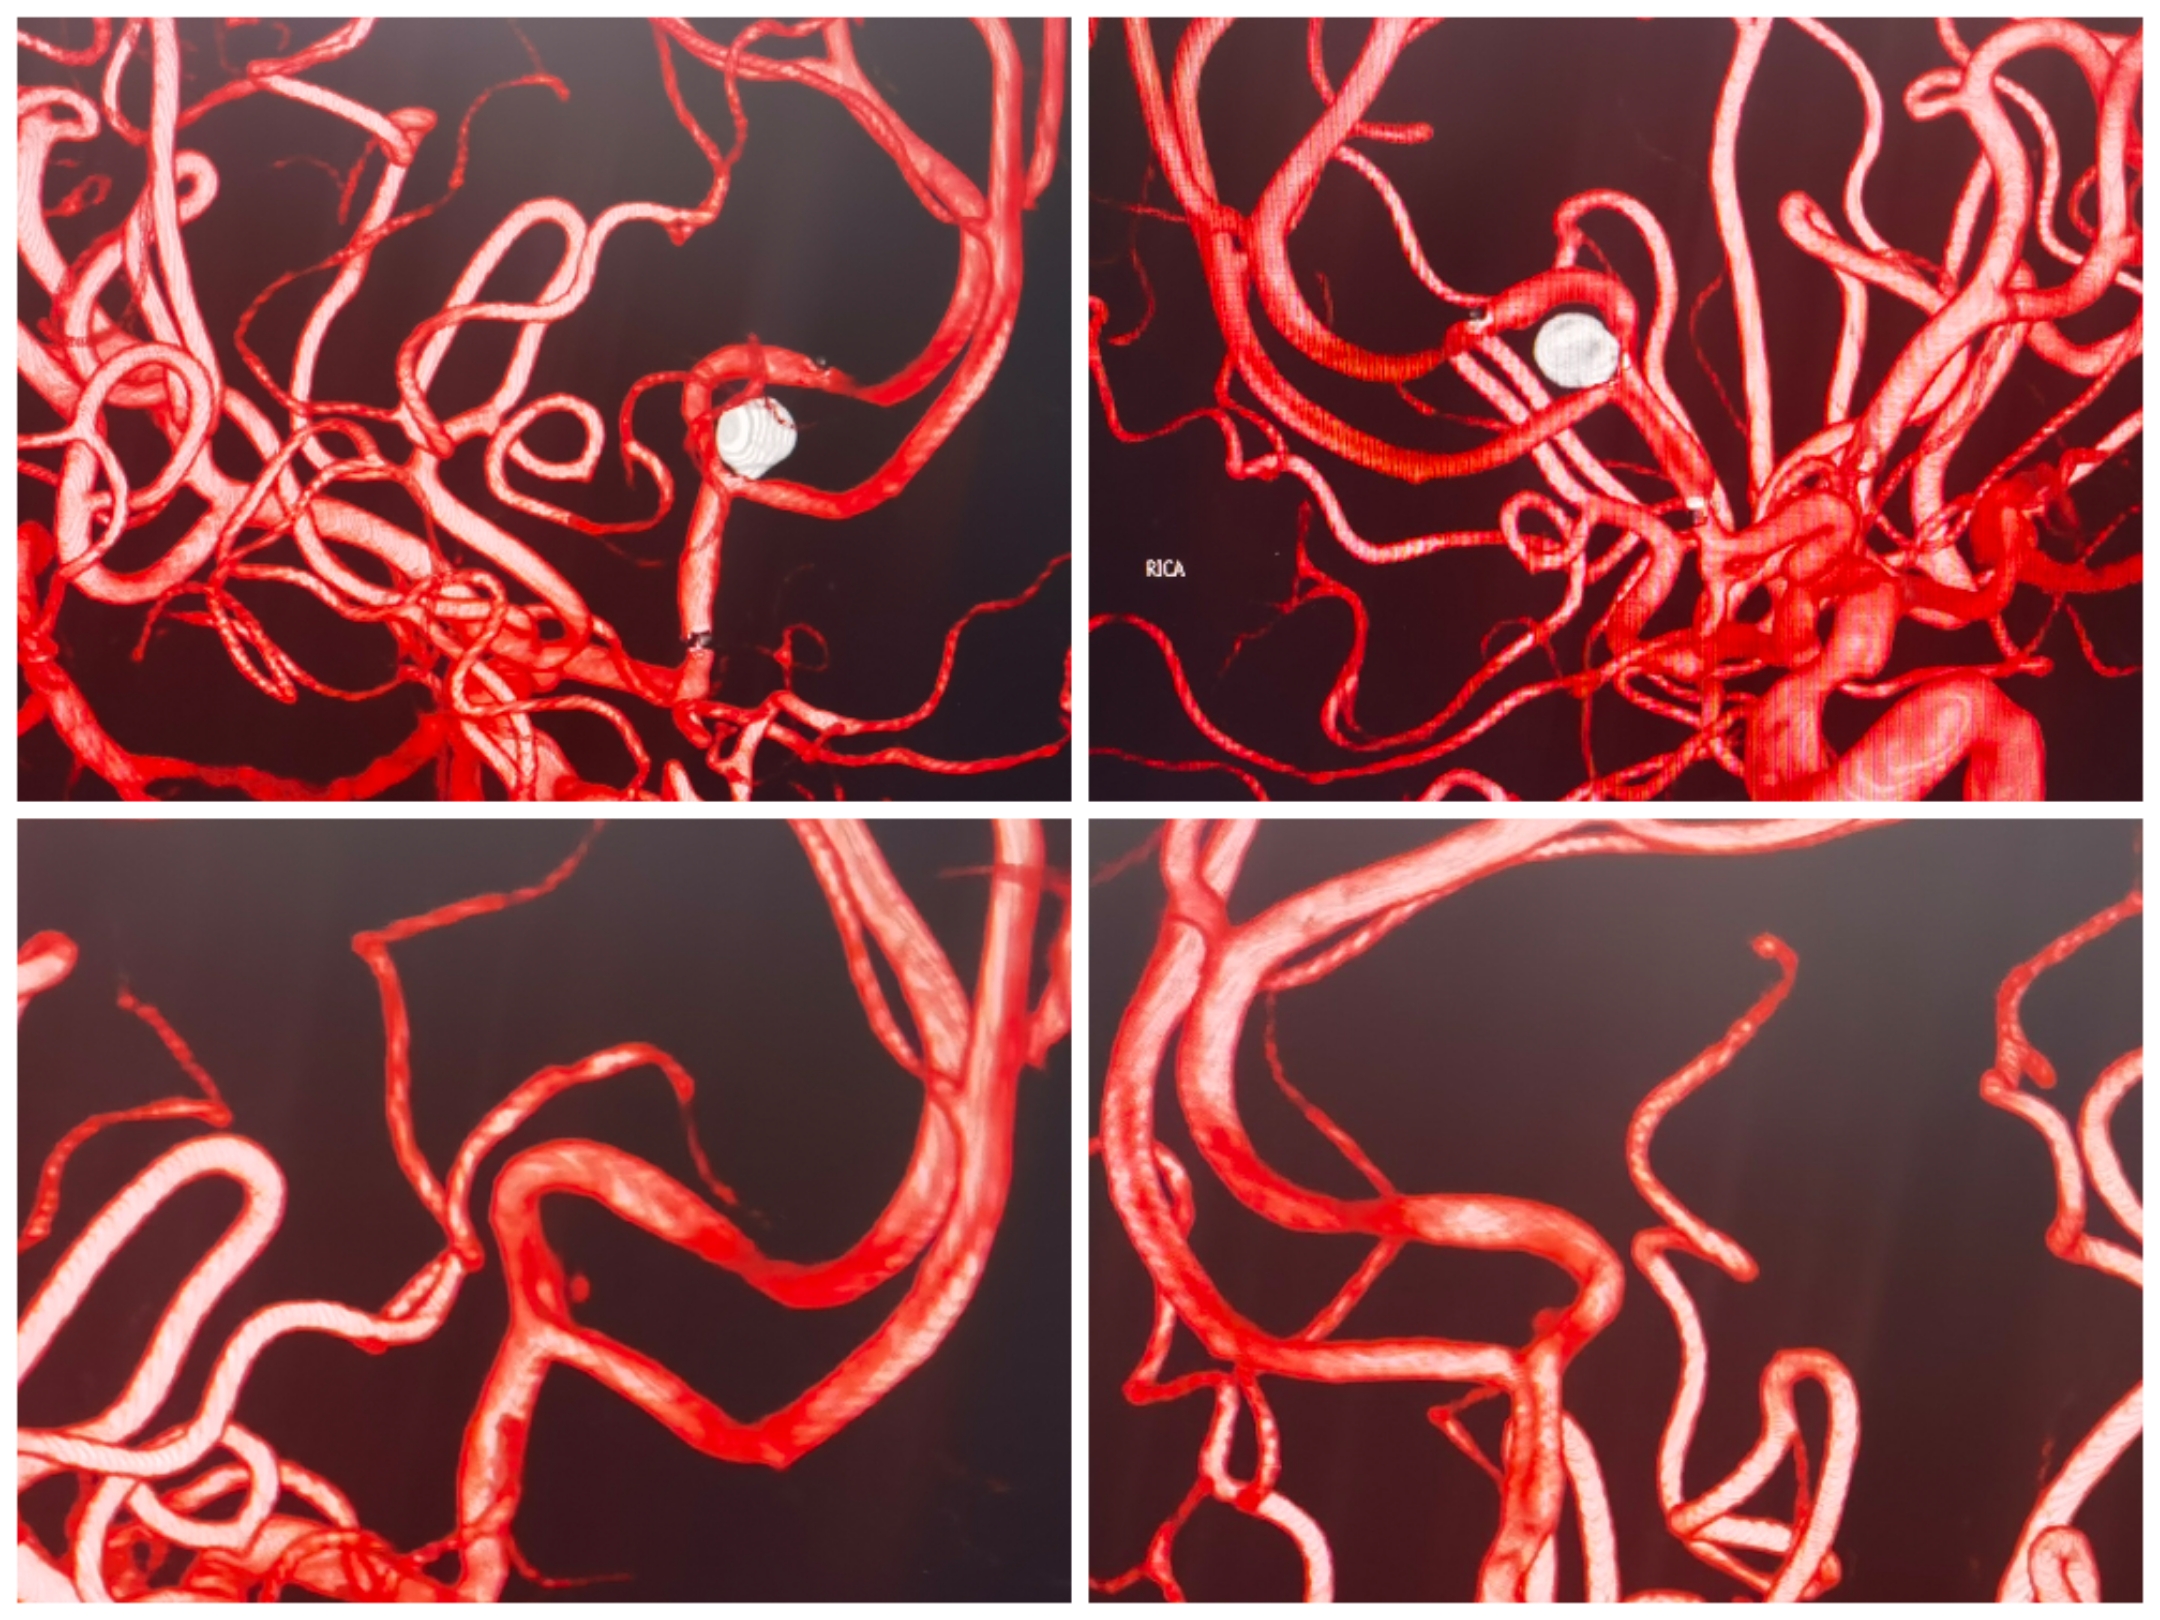

3D重建提示宽颈前交通动脉瘤,瘤颈偏向同侧A2。手术计划:支架置入同侧A2,利用开环支架穹窿效应保护对侧A2,行弹簧圈栓塞。WEB也是个不错的选择,可惜手上没有材料。

术后3D重建情况

术后支架CT重建